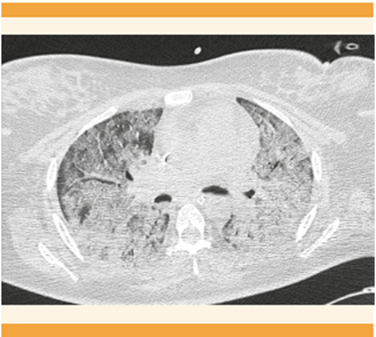

Continuó con deterioro ventilatorio y con saturación de oxígeno al 37%. Al colocarla en posición prona se consiguió que la saturación de oxígeno llegará al 83%, la gasometría con acidosis respiratoria (pH de 7.18, pCO2 61.9 mmHg, pO2 59.9 mmHg, HCO3 23.8 mEq/L); proteína C reactiva (PCR) 14.2 mg/dL, ferritina 237 ng/mL, leucocitos 9.7 x 103, hemoglobina de 12.3 g/dL, plaquetas 274 x 103 y glucosa 225 mg/dL. El cultivo de secreción bronquial reportó Klebsiela pneumoniae BLEE y el hemocultivo central Enterococcus faeclum. La evaluación con la escala SOFA obstétrica (Sequential Organ Failure Assessment) reportó 8 puntos, APACHE II-M (Acute Physiology and Chronic Health Evaluation II Modificado) con mortalidad estimada en 25%. Se integraron los diagnósticos de choque séptico de origen pulmonar, síndrome de insuficiencia respiratoria aguda severo, neumonía viral por SARS-CoV-2, insuficiencia respiratoria mixta con hipoxemia grave y acidosis respiratoria severa. Se indicó tratamiento con: fluconazol, meropenem, linezolid, heparina de bajo peso molecular y prednisona. Dos días después se logró regresar a la posición supina con saturación de oxígeno al 98%. Gradualmente se retiró el vasopresor y la sedación. Figuras 1y2

Figura 2 TAC contrastada en ventana pulmonar. Se observa una imagen en vidrio esmerilado multisegmentado con ocupación alveolar bilateral sugerente de neumonía viral (puntaje CORADS 5).